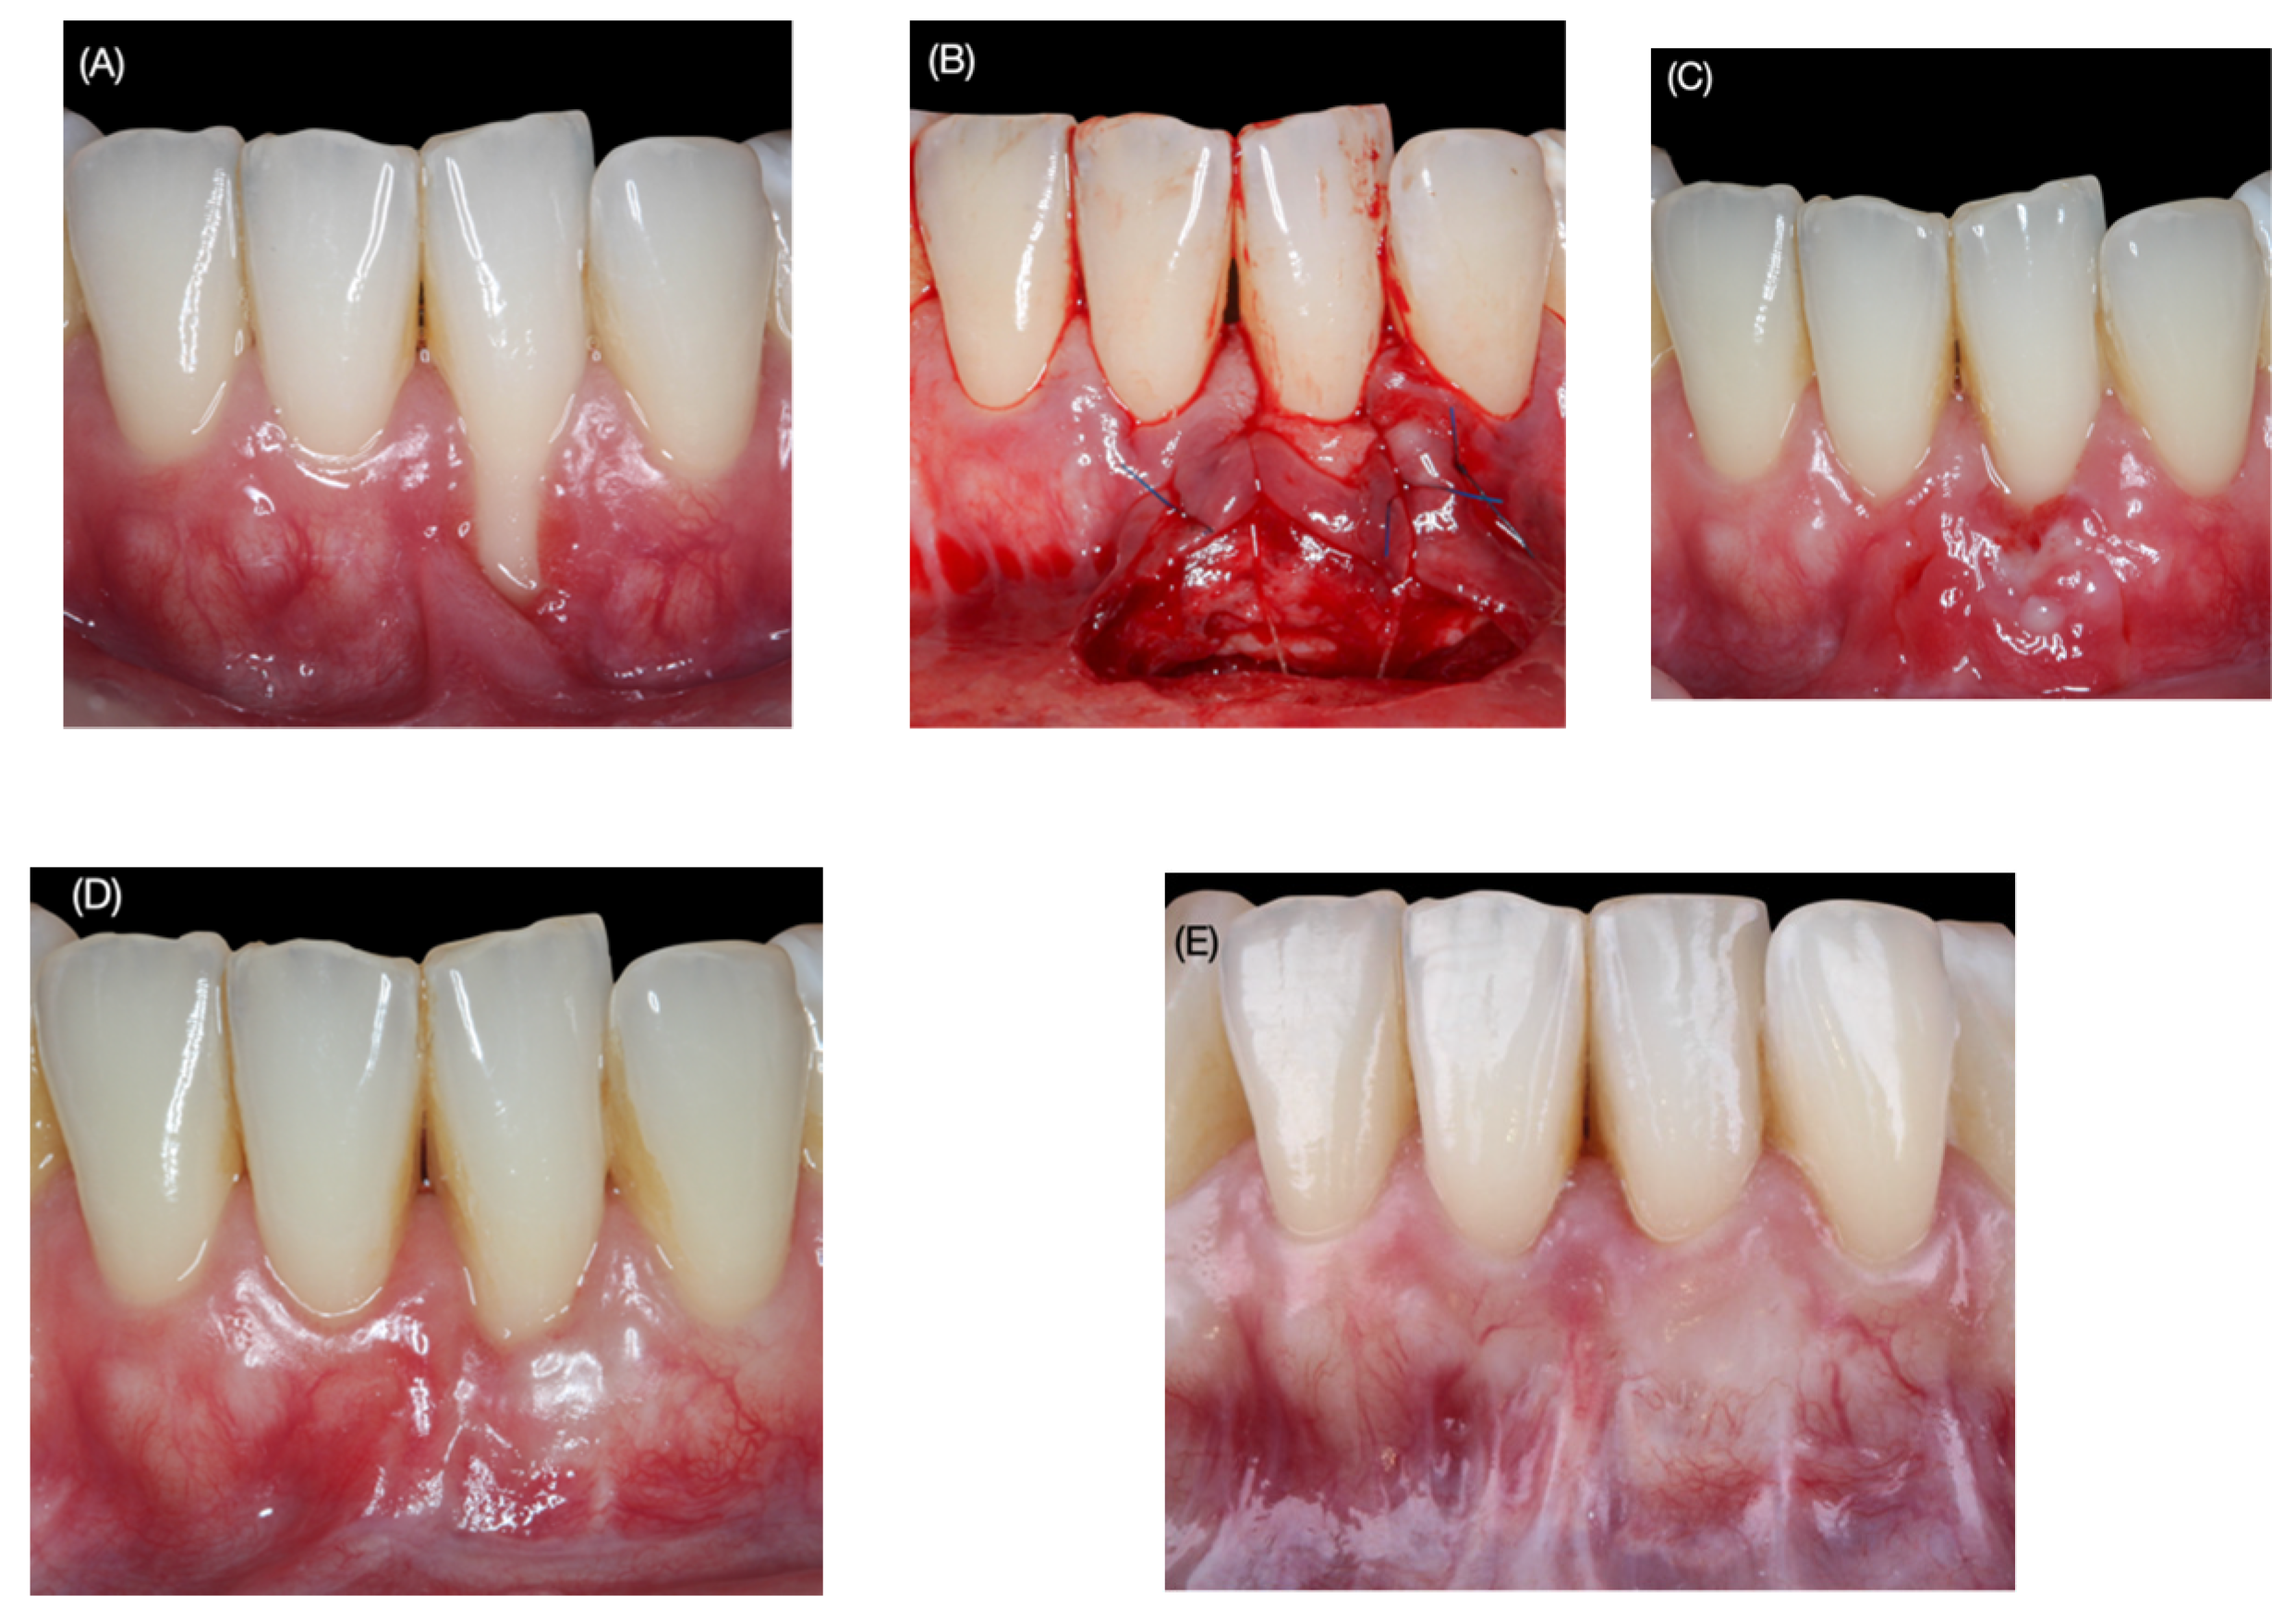

| Baseline and 36-Month Follow-Up | ||||

| Parameters | N | Mean ± SD | Range | p |

| GRD (mm) | 14 | |||

| Baseline | 14 | 3.2 ± 1.5 | 1–6 | |

| 36 months | 14 | 0.7 ± 0.8 | 0–2.5 | |

| Difference | 14 | 2.5 ± 1.5 | 1–6 | <0.01 |

| PD (mm) | 14 | |||

| Baseline | 14 | 1.7 ± 0.5 | 1–2 | |

| 36 months | 14 | 2.7 ± 1 | 1.5–5 | |

| Difference | 14 | 1.1 ± 1.0 | 0–6 | <0.01 |

| CAL (mm) | 14 | |||

| Baseline | 14 | 4.9 ± 1.5 | 3–8 | |

| 36 months | 14 | 3.4 ± 1.3 | 2.0–6.5 | |

| Difference | 14 | 1.5 ±1.4 | (−1)–4 | <0.01 |

| KTW (mm) | 14 | |||

| Baseline | 14 | 0.7 ± 1 | 0–4 | |

| 36 months | 14 | 2.6 ± 1.6 | 1–5 | |

| Difference | 14 | 1.9 ±1.7 | 0–5 | <0.01 |

| GT (mm) | 14 | |||

| Baseline | 14 | 0.0± 0.0 | 0–0 | |

| 36 months | 14 | 1.3 ± 0.3 | 1–2 | |

| Difference | 14 | 1.3 ± 0.3 | 1–2 | <0.01 |

| RES Score | |||||||||||

|---|---|---|---|---|---|---|---|---|---|---|---|

| Parameter | Level of Gingival Margin * | Marginal Tissue Contour ** | Soft Tissue Texture *** | Mucogingival Junction **** | Gingival Color ***** | ||||||

| TF | |||||||||||

| Score | 0 | 3 | 6 | 0 | 1 | 0 | 1 | 0 | 1 | 0 | 1 |

| n. (%) | 1 | 4 | 9 | 4 | 10 | 8 | 6 | 4 | 10 | 3 | 11 |

| (7.1) | (28.6) | (64.3) | (28.6) | (71.4) | (57.1) | (42.9) | (28.6) | (71.4) | (21.4) | (78.6) | |

| Total Score Average Mean (SD) | 7.4 (2.7) | ||||||||||

| Median (IQR) | 8.5 (4) | ||||||||||